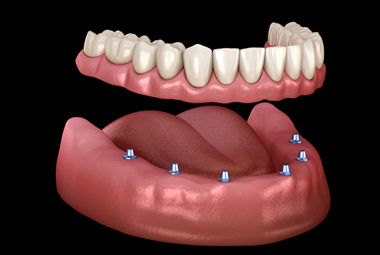

Overdentures